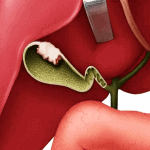

Ung thư túi mật chủ yếu là ung thư biểu mô, hiếm gặp, đa phần ở người có tuổi. Nữ nhiều hơn nam (4/1). Yếu tố nguy cơ: sỏi túi mật, polyp túi mật, túi mật hóa sứ. Hai dạng tổn thương: thể thâm nhiễm phát triển từ đáy hay cổ lan rộng một cách nhah chóng sang rốn gan hoặc nhu mô gan. Thể u sùi biểu hiện bằng khối nhô vào lòng túi mật, phát triển và lan rộng…